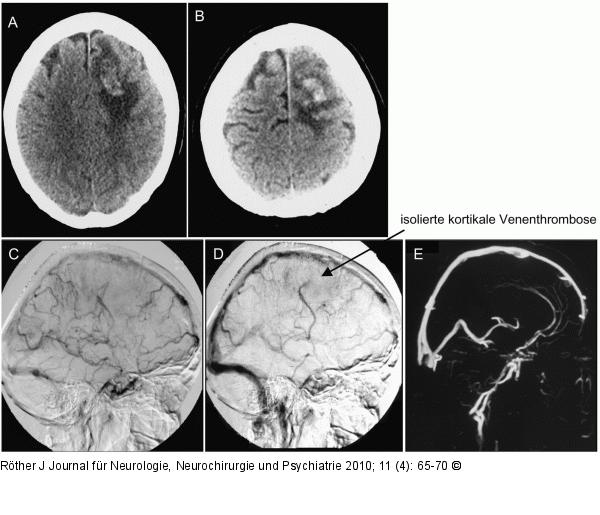

Abbildung 2a-e: SVT Bildgebung der SVT: Isolierte kortikale Venenthrombose bei 32-jähriger Patientin mit Kopfschmerzen, Übelkeit und Erbrechen. Im Verlauf nach 3 Tagen generalisierte Anfälle mit fokaler Einleitung. Nach 5 Tagen beinbetonte Hemiplegie R. Faktor-V-Gen-Mutation und pathologische APC-Resistenz. A, B: CT mit Stauungsblutung hochfrontal links; C, D: Digitale Subtraktionsangiographie mit Verschluss einer kortikalen Vene; E: MR-Venographie mit normalem Befund. |

Bildgebung der SVT: Isolierte kortikale Venenthrombose bei 32-jähriger Patientin mit Kopfschmerzen, Übelkeit und Erbrechen. Im Verlauf nach 3 Tagen generalisierte Anfälle mit fokaler Einleitung. Nach 5 Tagen beinbetonte Hemiplegie R. Faktor-V-Gen-Mutation und pathologische APC-Resistenz. A, B: CT mit Stauungsblutung hochfrontal links; C, D: Digitale Subtraktionsangiographie mit Verschluss einer kortikalen Vene; E: MR-Venographie mit normalem Befund. |